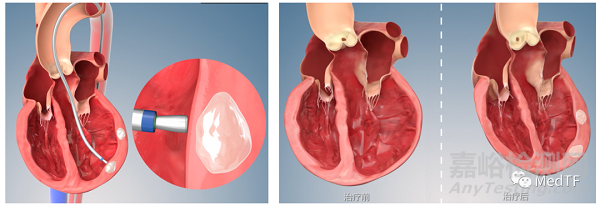

經(jīng)導(dǎo)管心內(nèi)膜注射植入性海藻酸鹽水凝膠

植入性海藻酸鹽水凝膠:通過增厚心肌壁,為室壁提供力學(xué)支撐,降低室壁應(yīng)力,維持心臟相對(duì)良好的形態(tài)、尺寸和力學(xué)性質(zhì)(如左室功能)等,最終減緩甚至逆轉(zhuǎn)心室的擴(kuò)張,改善心臟的生理功能。另外,海藻酸鹽水凝膠具有良好的生物相容性和生物惰性,能夠在人體內(nèi)長期存在,維持治療作用。

經(jīng)導(dǎo)管心內(nèi)膜注射系統(tǒng):心內(nèi)膜注射系統(tǒng)可保證海藻酸鹽水凝膠被順利植入心臟,發(fā)揮治療作用。其經(jīng)股動(dòng)脈入路,通過DSA(數(shù)字減影血管造影)與TEE(經(jīng)食道超聲心動(dòng)圖)雙重導(dǎo)航定位,確保水凝膠安全且有效地遞送。通過造影劑和超聲雙重確認(rèn)注射針是否刺進(jìn)心室壁且避開血管。植入后,在注射點(diǎn)區(qū)域,通過TEE可見強(qiáng)化回聲。